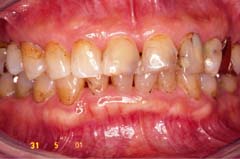

■ダイレクトベニア■

施術前

施術後

前歯の2番目の歯をご覧下さい。

施術前と施術後では、見た目はもとより咬み合わせも良くなっているのがおわかり頂けます。